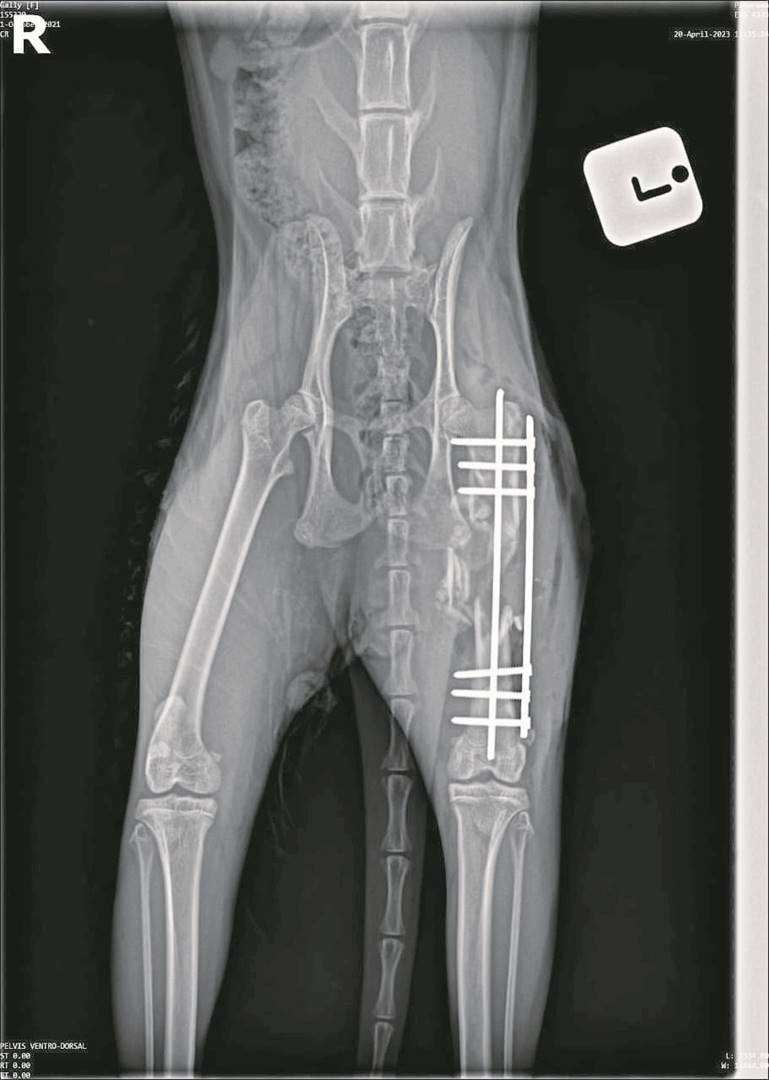

Volgens haar moes ’n gesin in Heldervue onlangs ’n groot trauma deurmaak nadat een van hul katte dood is en hul ander kat gewond is nadat die troeteldier glo twee keer met ’n windbuks geskiet is.

“Die gesin se een kat, genaamd Parrot, sterk tans by die huis aan nadat hy weggehardloop en eers op Maandag 20 Maart weer by die huis aangekom het,” verduidelik die inspekteur.

Die eienaar het bloed gesien en die kat veearts toe geneem.

“Die kat het twee wonde aan die lyf (aan weerskante van die lyf) gehad. Volgens die familie het die veearts gesê dit is moontlik pellets uit ’n windbuks,” sê Mostert.